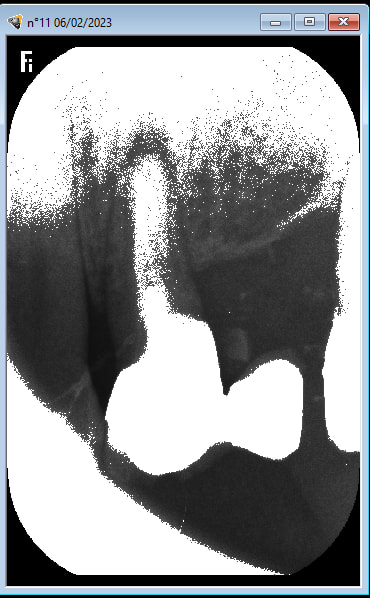

bon je crois que je suis poursuivi par la malédiction du rayon X

en ce moment je prends une radio , je la mets dans le carestream CS 7200 , la radio apparait elle est mimi , ça dure 1/2 seconde et piouff toute pourrie .

sinon , quand c est bien exposé , il y a une barrette qui passe au vert .

eh bien pour que ça devienne vert , il faut que je règle le canon sur 0.4 , c est énorme .

ça dure longtemps : pouuuuuuuuuuuuuuuuuuuuucouic , je te le fais en temps réel .